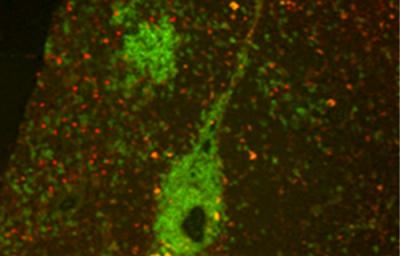

The Garvan lab members worked with mice genetically modified to express high levels of 'BAFF', a substance that increases survival of B cells. The higher number of B cells overall allowed researchers to track the activity of B cells in the thymus.

"Our experiments showed clearly that B cells participated in the creation of regulatory T cells – the more B cells that were in the thymus, the higher the number of regulatory cells generated. That direct correlation raises interesting possibilities."